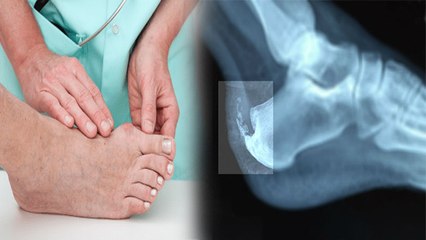

टीबी एक संक्रामक रोग है। यह माइकोबैक्टीरियम ट्यूबरकुलोसिस जीवाणु के कारण होता है। दुनिया भर में होने वाले मौतों के कारणों में टीबी भी प्रमुख है। टीबी मुख्य रूप से श्वसन तंत्र या फेफड़ों और पाचन तंत्र को प्रभावित करता है। लेकिन कुछ मामलों में यह शरीर के अन्य अंगों में हो सकता है। यह नाखूनों और बालों के अलावा खून के माध्यम से शरीर के सभी अंगों तक फैल सकता है। टीबी हड्डियों में भी हो सकता है, तब इसे बोन टीबी या हड्डियों में टीबी कहा जाता है। बोन टीबी को मस्कुलोस्केलेटल टीबी भी कहा जाता है। बोन टीबी को मस्कुलोस्केलेटल टीबी के नाम से भी जाना जाता है। डॉक्टर हेमलता अरोड़ा बताती हैं कि बोन टीबी तब होता है, जब टीबी का बैक्टीरिया फेफड़ों से हड्डियों या जोड़ों में फैल जाता है। यह आमतौर पर समृद्ध संवहनी आपूर्ति के कारण हड्डियों के बीच में शुरू होता है। यह शरीर के किसी भी हड्डी को संभावित रूप से प्रभावित कर सकता है। लेकिन रीढ़ की हड्डी, पीठ इससे सबसे ज्यादा प्रभावित होते हैं। बोन टीबी हाथों के जोड़ों, कोहनियों और कलाई को भी प्रभावित करता है। टीबी का बैक्टीरिया खून के माध्यम से अन्य अंगों तक फैलता है। br br TB is an infectious disease. It is caused by the bacterium Mycobacterium tuberculosis. TB is also one of the leading causes of death worldwide. TB mainly affects the respiratory system or lungs and digestive system. But in some cases it can happen in other parts of the body. It can spread to all parts of the body through the blood except nails and hair. TB can also occur in the bones, then it is called bone TB or TB in the bones. Bone TB is also called musculoskeletal TB. Bone TB is also known as musculoskeletal TB. Doctor Hemlata Arora explains that bone TB occurs when the TB bacteria spread from the lungs to the bones or joints. It usually starts in the middle of the bones because of the rich vascular supply. It can potentially affect any bone in the body. But the spine , back are most affected by this. Bone TB also affects the joints of the hands, elbows and wrists. TB bacteria spread through the blood to other organs.